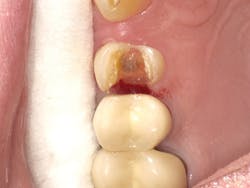

Case Three is a challenging crown repair on a medically compromised patient. The preoperative image shows decay at the buccal margin of an anterior abutment to a bridge (figure 11). Following excavation with the Lite Touch laser (figure 12), we decided to use Futurabond U in a self-etch technique followed by layering Admira Fusion in two increments. The first increment was an opaque layer, using shade OA2 to attempt to block out the gray margin of the porcelain-fused-to-metal crown (figure 13). After light-curing that layer, we applied shade A1 and light-cured and polished the restoration, achieving a highly esthetic result given the difficulty of the situation (figure 14).

Figure 14